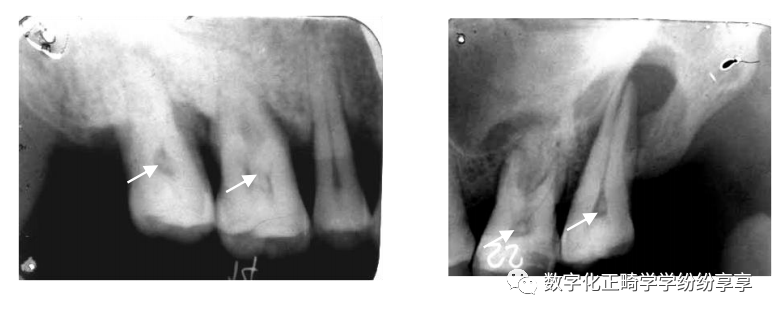

埋伏牙

曲面断层片怎么看正畸【曲面断层片(全景片)】如何解读和查看:牙周?牙体?牙髓?关节?_https://www.jmylbn.com_新闻资讯_第2张

龋齿情况

曲面断层片怎么看正畸【曲面断层片(全景片)】如何解读和查看:牙周?牙体?牙髓?关节?_https://www.jmylbn.com_新闻资讯_第3张